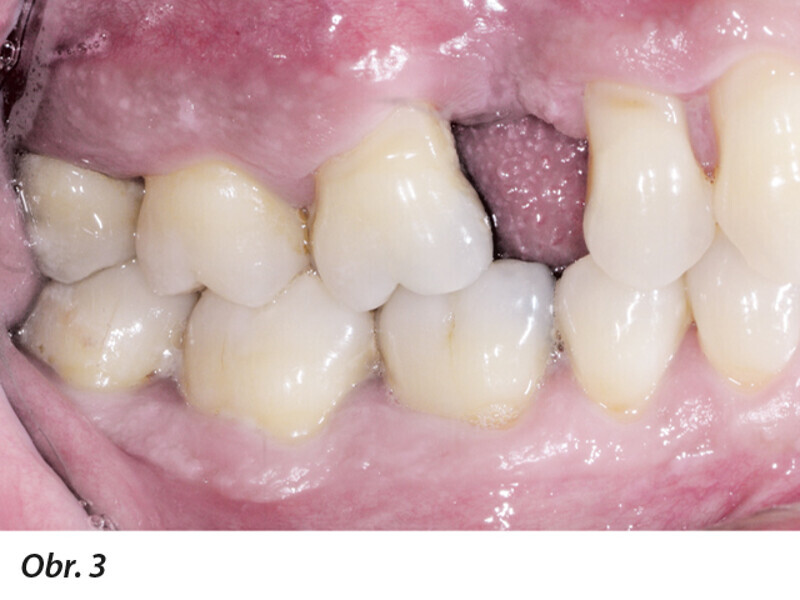

Multidisciplinární léčba u pacienta se závažnou parodontitidou